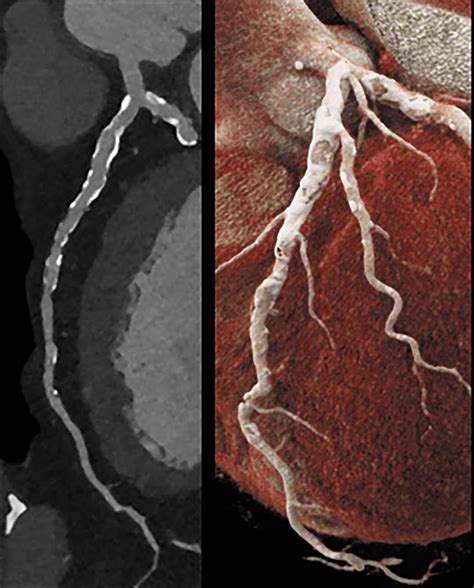

At its core, a Cardiac CT scan is an imaging test that allows cardiologists and radiologists to see if your coronary arteries are narrowed or blocked by plaque buildup—a condition known as atherosclerosis. Unlike traditional stress tests, which provide functional information about how your heart handles exertion, a cardiac CT provides anatomical information. It captures images of the heart while it is beating, using sophisticated gating technology to synchronize the image acquisition with your heart rhythm.

This technology is particularly effective at identifying early-stage heart disease before symptoms manifest. By visualizing the calcified and non-calcified plaque within the arterial walls, physicians can initiate preventative treatments far earlier than previously possible.

Once the scan is complete, the images are sent to a radiologist or a specialized cardiologist who analyzes the anatomy of your coronary arteries. They will look for the presence and extent of plaque, the degree of arterial narrowing (stenosis), and the presence of any calcium deposits. You will receive a formal report, and your primary doctor will discuss the findings with you to determine the next steps in your care plan. Depending on the findings, these steps may include lifestyle modifications, cholesterol-lowering medication, or further diagnostic testing.